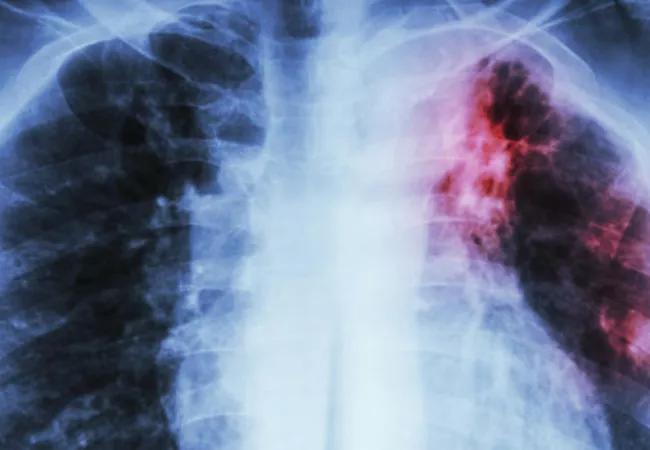

How to Treat Idiopathic Pulmonary Fibrosis

An overview of available treatment modalities

Idiopathic pulmonary fibrosis (IPF) is a devastating and fatal lung disease that generally affects older adults. Primary care physicians are uniquely positioned to encounter patients with IPF, whether because of a patient complaint or as an incidental finding on computed tomography. Here we offer an overview of available treatments; click here for an overview of the disease and here for information on diagnosis.